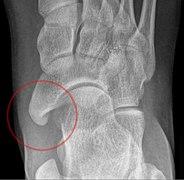

An accessory navicular bone is an accessory bone of the foot that occasionally develops abnormally in front of the ankle towards the inside of the foot. This bone may be present in approximately 2-21% of the general population and is usually asymptomatic.[1][2][3] When it is symptomatic, surgery may be necessary.

Accessory navicular bone may cause a continuous stretch and stress on the tibialis posterior tendon which can progress to chronic disabling pain and may cause tendon rupture or secondary flat foot deformity; when this occurs this condition is commonly known as accessory navicular syndrome.[4]

The Geist classification divides the accessory navicular bones into three types.[3]

• Type 2: Triangular or heart-shaped ossicle measuring up to 12 mm, which represents a secondary ossification center connected to the navicular tuberosity by a 1–2 mm layer of fibrocartilage or hyaline cartilage. Portions of the posterior tibialis tendon sometimes insert onto the accessory ossicle, which can cause dysfunction, and therefore, symptoms.

• Type 3: A cornuate navicular bone represents an enlarged navicular tuberosity, which may represent a fused Type 2 accessory bone. Occasionally symptomatic due to bunion formation.

Radiological images